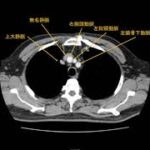

오늘부터 국제성모병원 심장혈관흉부외과 류상완 원장의 코너가 새롭게 시작됩니다. 첫 번째 ...